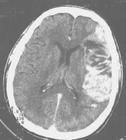

1.腦CT掃描腦梗死的腦CT掃描的主要表現為:①病灶的低密度:是腦梗死重要的特徵性表現此徵象可能系腦組織缺血性水腫所致②局部腦組織腫脹:表現為腦溝消失腦池、腦室受壓變形,中線結構向對側移位即腦CT掃描顯示有占位效應此徵象可在發病後4~6h觀察到③緻密動脈影:為主要腦

腦梗死2.腦MRI檢查能較早期發現腦梗死,特別是腦幹和小腦的病灶。T1和T2馳像時間延長加權圖像上T1在病灶區呈低信號T2呈高信號腦MRI檢查能發現較小的梗死病灶腦MRI彌散成像能反映新的梗死病變。MRI在缺血性腦梗死早期診斷和鑑別診斷的評價中已顯示出優勢,近年來超導高檔磁共振設備投入臨床套用,基於平面回波(EPI)技術的磁共振彌散加權成像(DWI)及血流灌注加權成像(PWI)的套用,對腦梗死的早期診斷,甚至在急性腦梗死區血流灌注變化以及病理生理過程的相關性研究都取得了一定進展